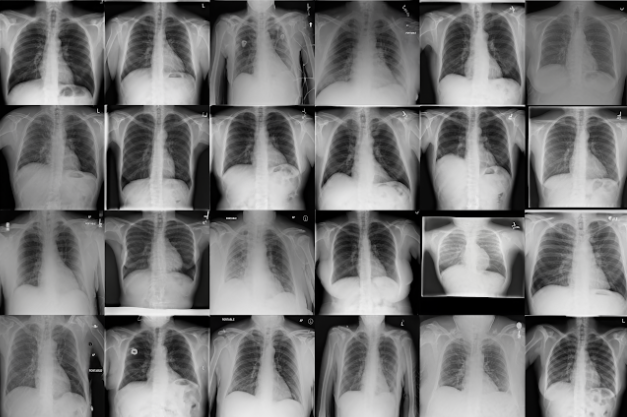

Since we started Synthetaic, we have expanded the concept as we realized that by combining both 3D modeling and novel generative AI we could grow data faster, cheaper, and in a way more aligned with training state-of-the-art AI than any other data synthesis technique. These days we are generating human cancer microscopy images for inter-operative brain surgery decision making, growing chest x-ray images for COVID-19 detection, synthesizing aerial imagery for conservation projects, and creating data for several unsolved security intelligence needs. In each of these cases the data is indistinguishable from real images, but nearly instantly generated on our servers, and we can use this data to train AI models that outperform the current state-of-the-art.

自从开始Synthetaic以来,我们扩展了这一概念,因为我们意识到,通过将3D建模与新颖的生成型AI结合起来,我们可以更快,更便宜地增长数据,并且以与其他任何类型的先进AI训练方式更加一致数据综合技术。 这些天来,我们正在生成用于人类脑部手术决策的人类癌症显微镜图像,用于COVID-19检测的胸部X射线图像的增长,用于保护项目的航空图像的合成,以及为一些未解决的安全情报需求创建数据。 在每种情况下,数据都无法与真实图像区分开,但是几乎是在我们的服务器上即时生成的,我们可以使用这些数据来训练优于当前最新技术的AI模型。